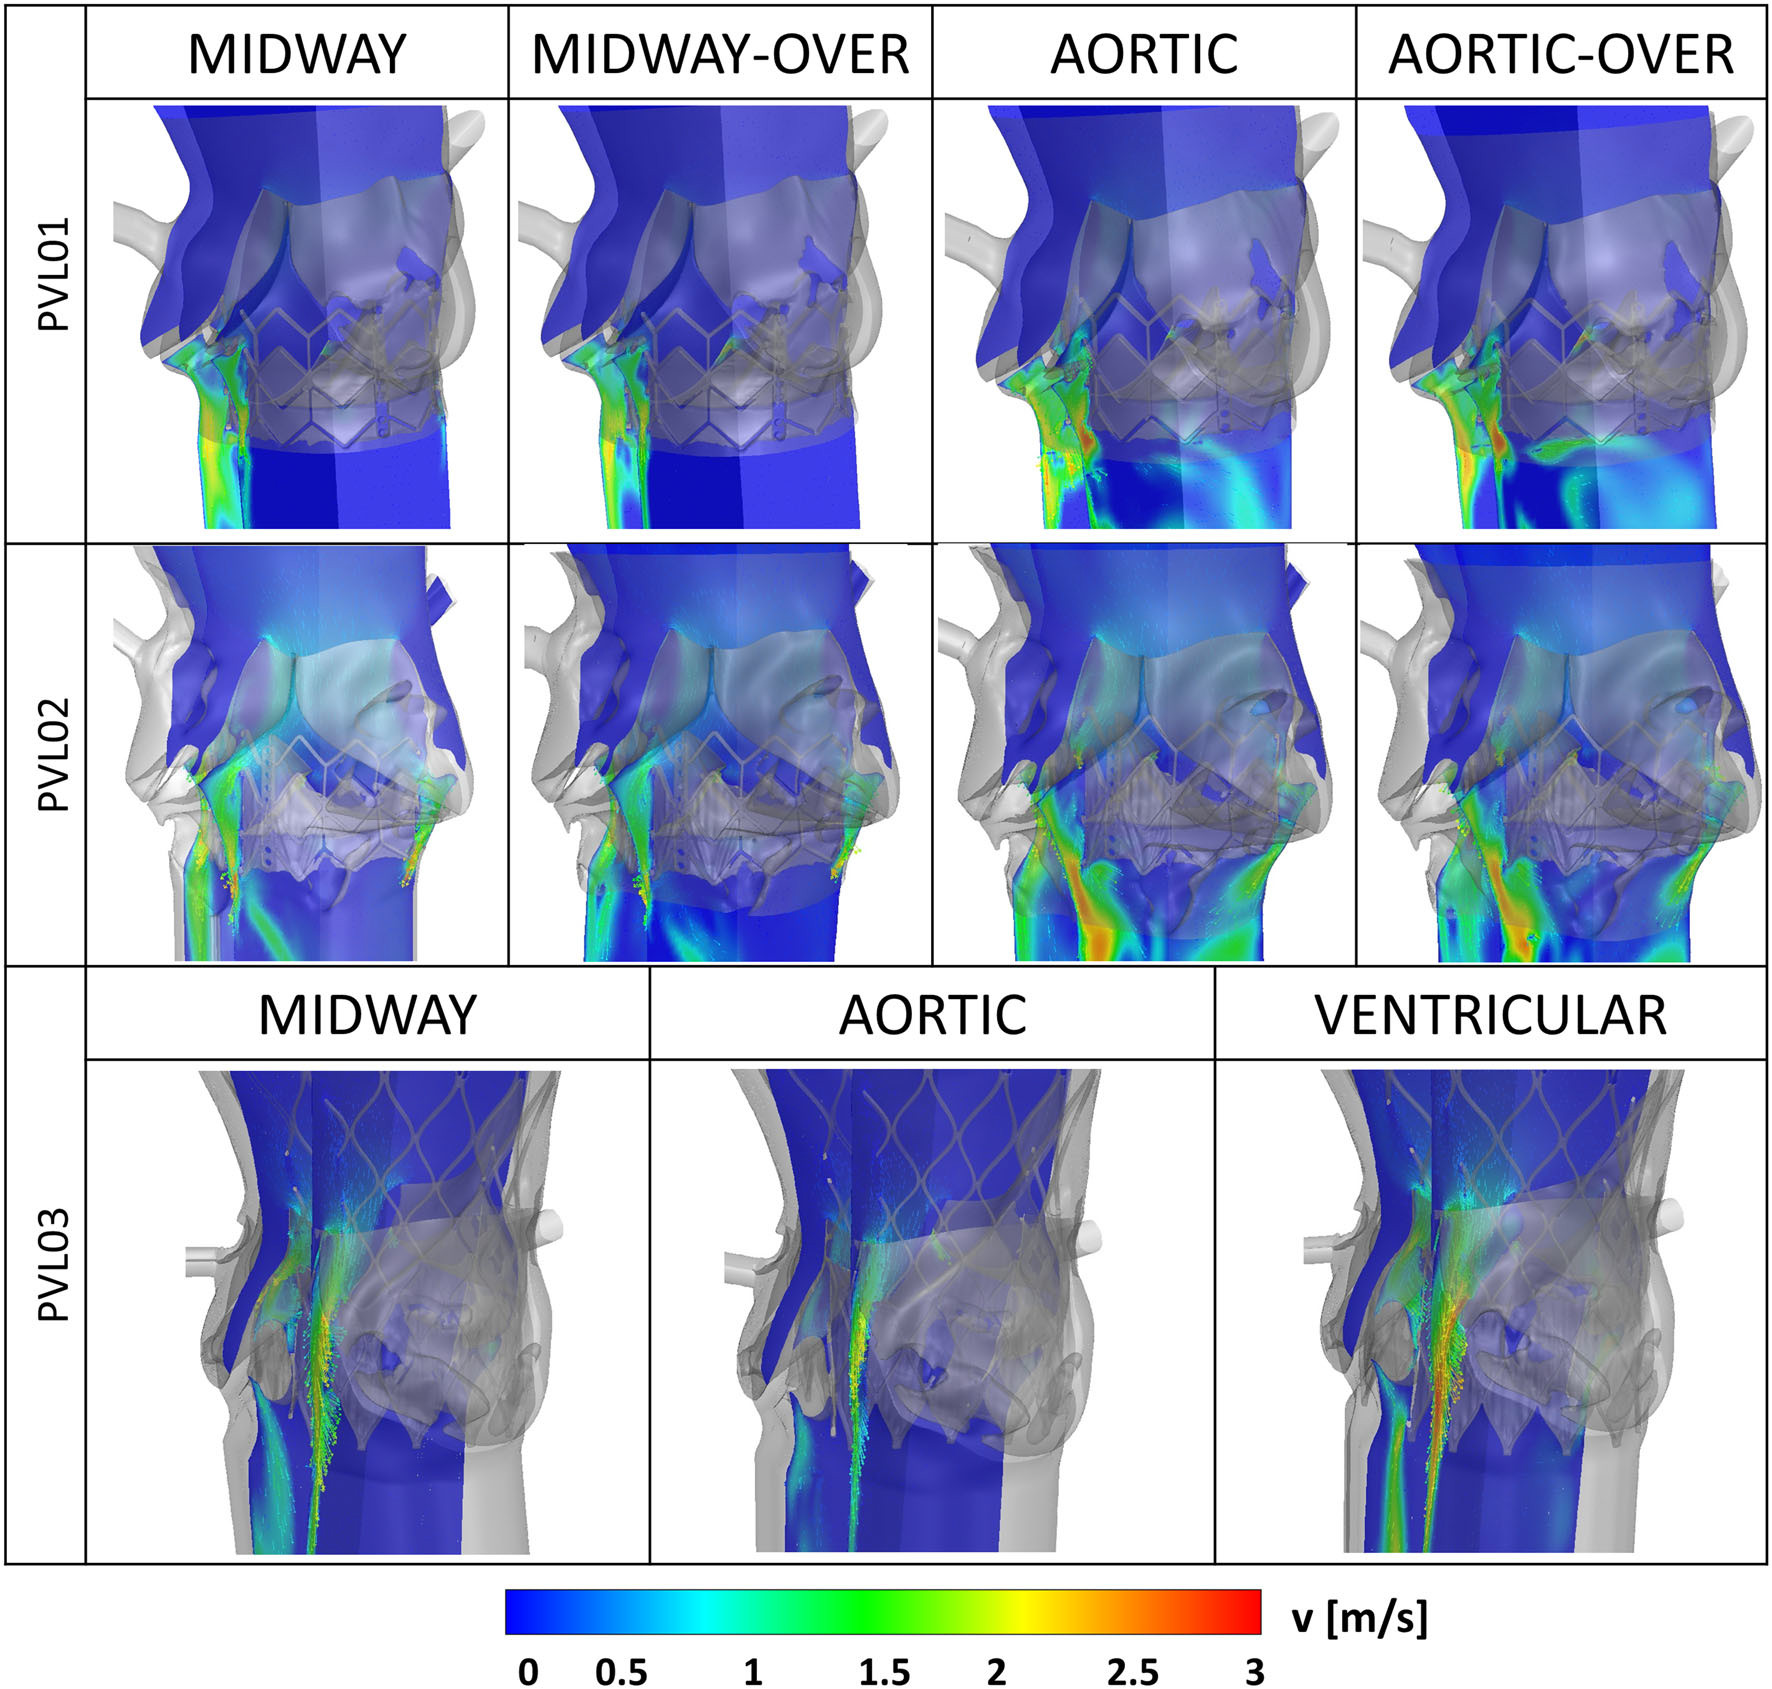

Evolving from in-vitro models to in-silico simulations

In order to study the resulting paravalvular leak flows in greater detail, we developed a protocol to µCT scan the deployed TAVR devices inside the CAVD replicas. Segmentation of the deployed geometry yeilds an ideal numerical domain to perform detailed CFD analysis (ANSYS Fluent) on the leak flows.

Lastly platelet-like particles are seeded with a DPM model in the ventricle geometry and tracked for 3 cycles. Showing the first evidence of the possiblity of platelet to enter the PVL domain during systole and the potential of repeated reincorporation into the PVL flows over the successive cycles.